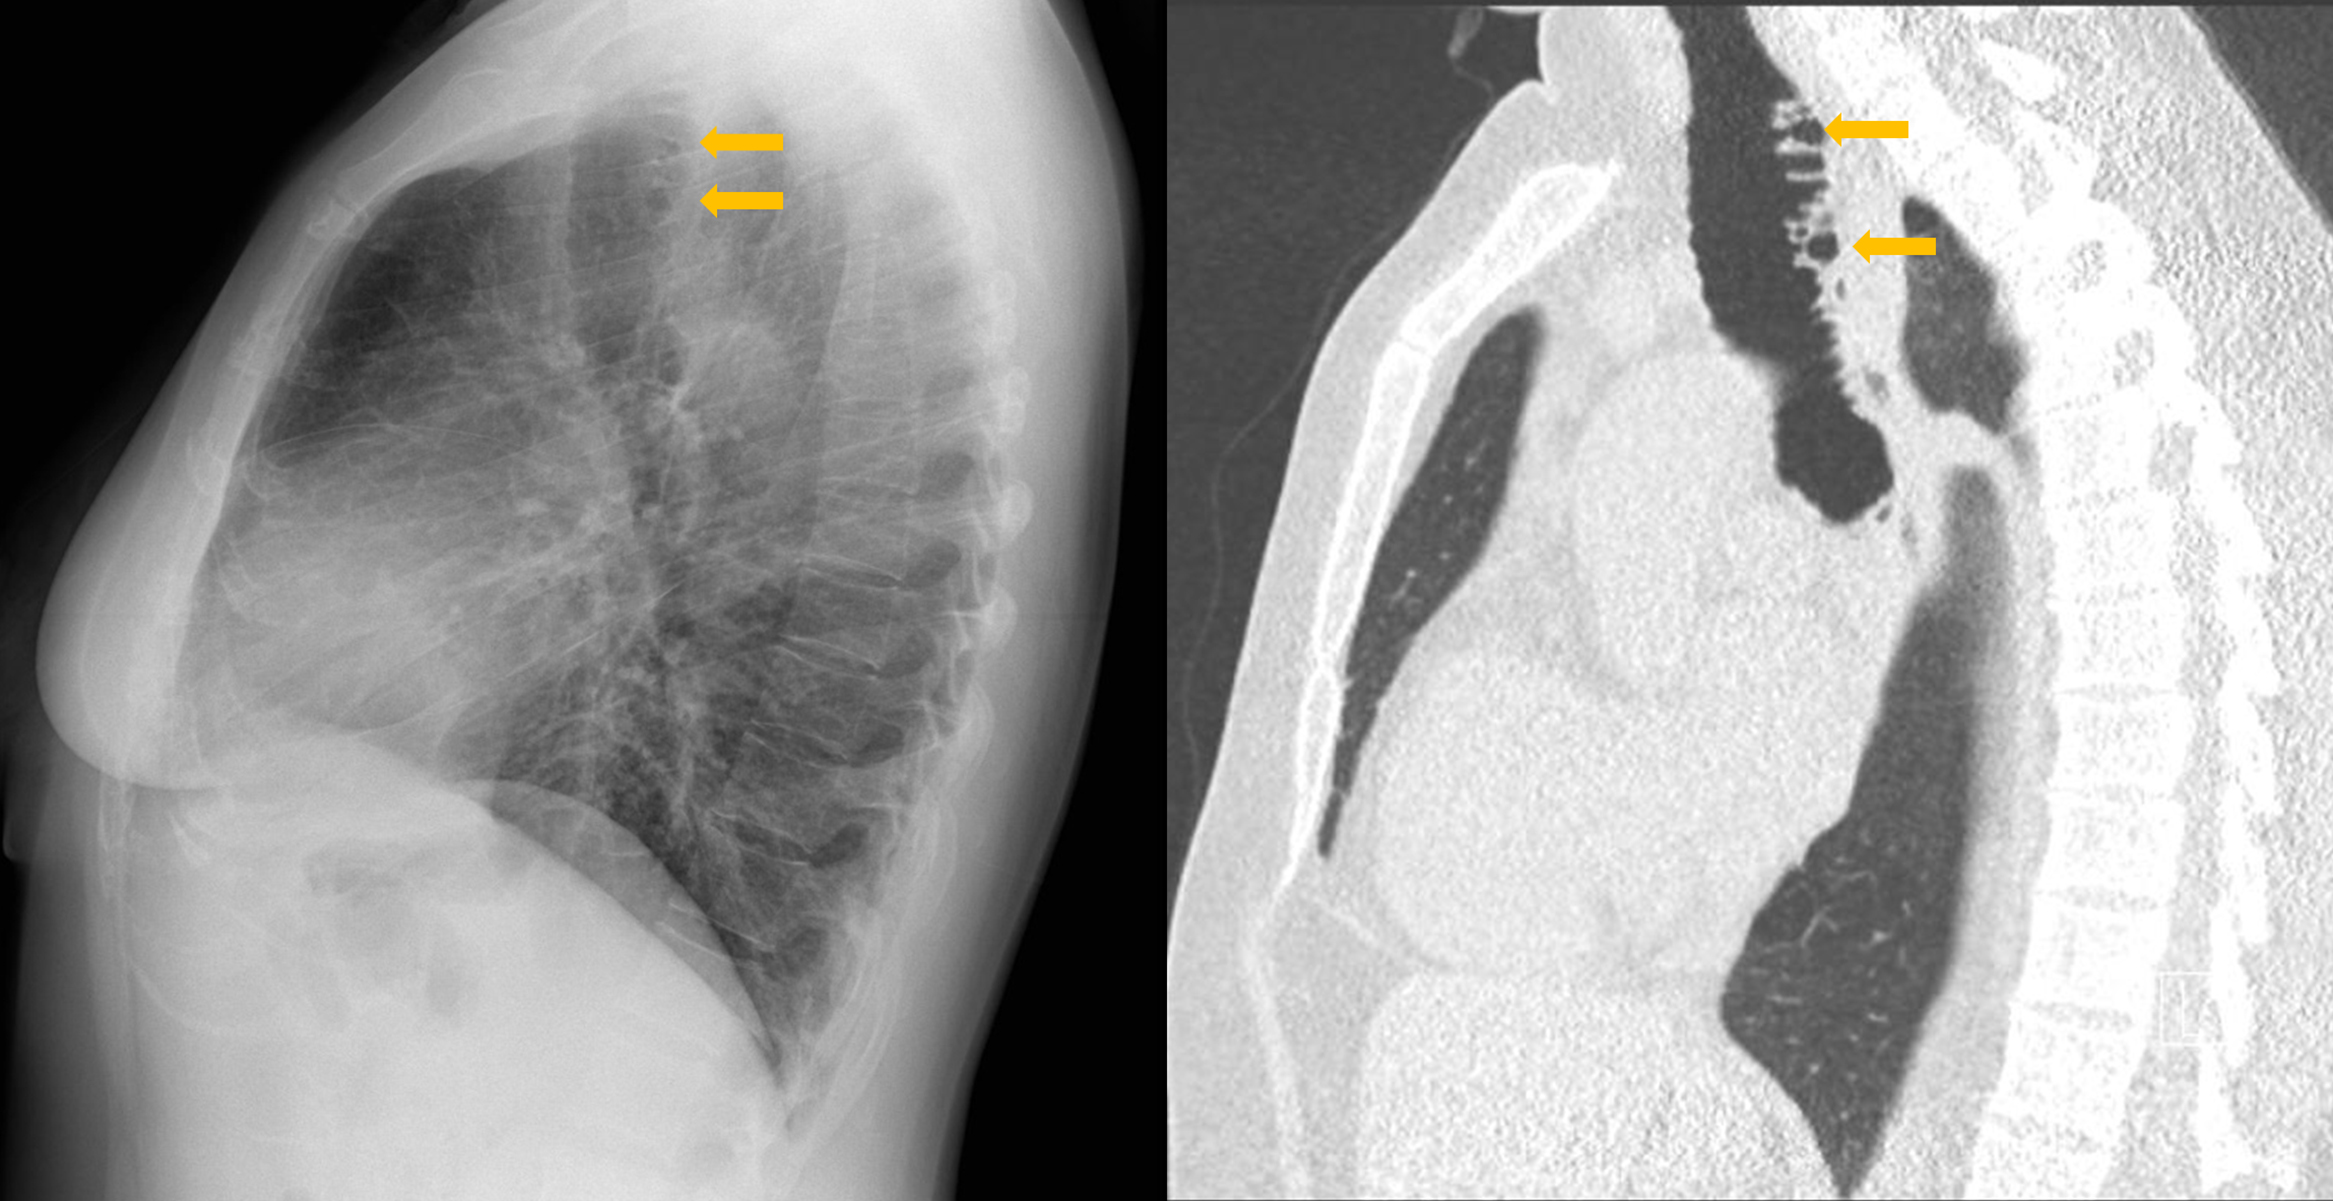

Figure 2

Tracheal diverticulosis: sagital CXR and CT comparison.